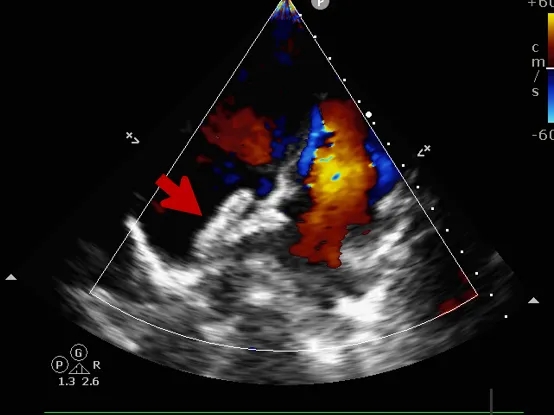

锁定后评估

心尖四腔心切面可见封堵器形态良好

主动脉短轴切面可见封堵器呈“Y”字型抱住主动脉

彩色多普勒血流成像显示无残余分流存在

释放后评估

封堵器位置正确、形态良好

封堵成功